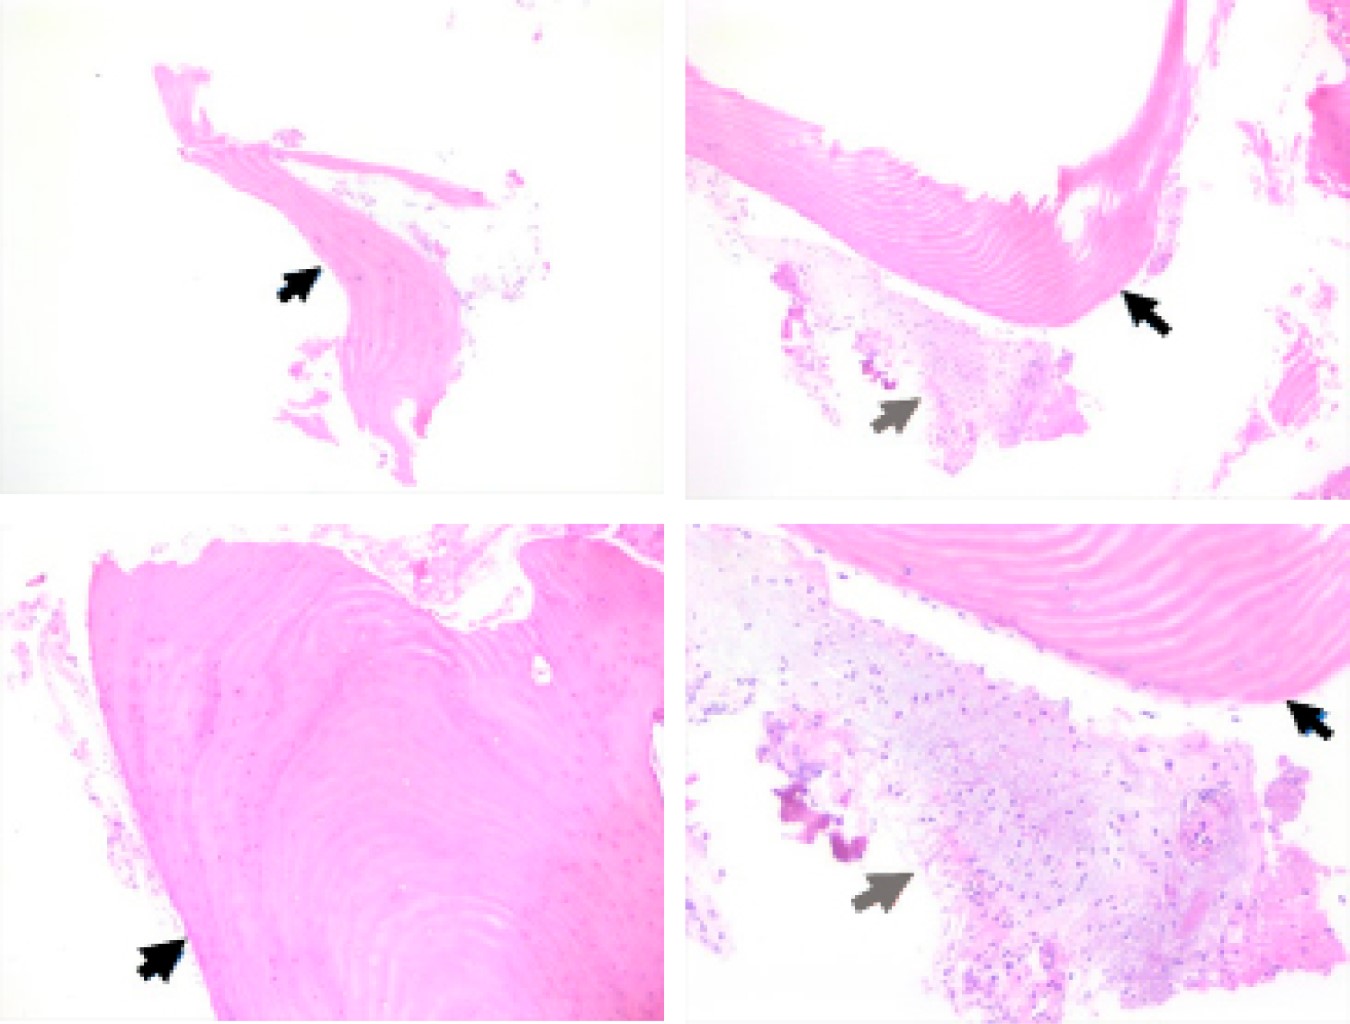

External auditory canal osteoma

Osteomas of the external auditory canal are benign tumors of bone tissue, slow growing, unilateral and initially asymptomatic so there are no real data on their incidence and frequency. The location of the osteomas is lateral to the isthmus of the external auditory canal and originate from pre-bone connective tissue located in the tympanosquamous or tympanomastoid sutures. The most common complication of osteoma is the formation of cholesteatoma and erosion of the duct walls. Treatment depends on the size of the lesion, and it can be conservative or surgical. We present a case of a 30-year-old female with an osteoma in the right external auditory canal diagnosed and treated at the Mexican Institute of Otology and Neurotology of Mexico City and a literature review of case reports and case series with this pathology published until April 2021.

Figure 2